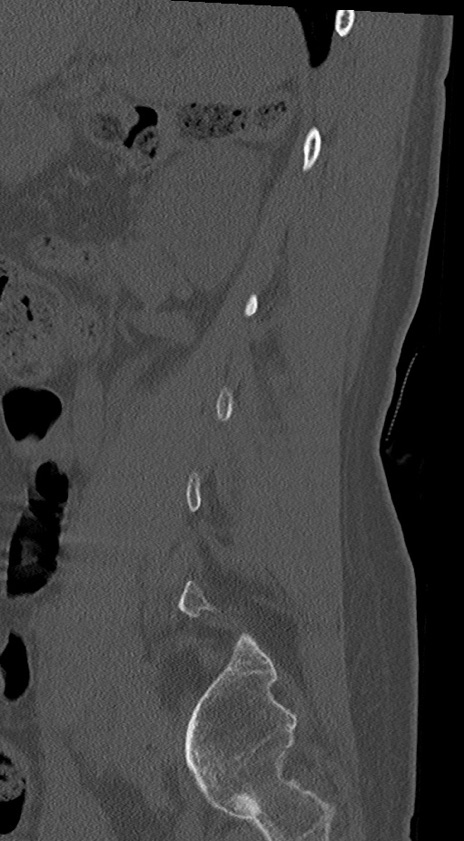

【整形】TIPS症例4 腰椎CT(矢状断像)

腰椎CT

冠状断像